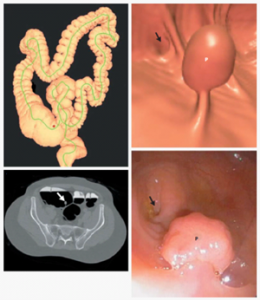

- The highly productive CT Colonography program is led by Perry J Pickhardt, MD and David Kim, MD. Dr. Pickhardt has produced over 250 publications in this area with multiple papers receiving over 1,000 citations.